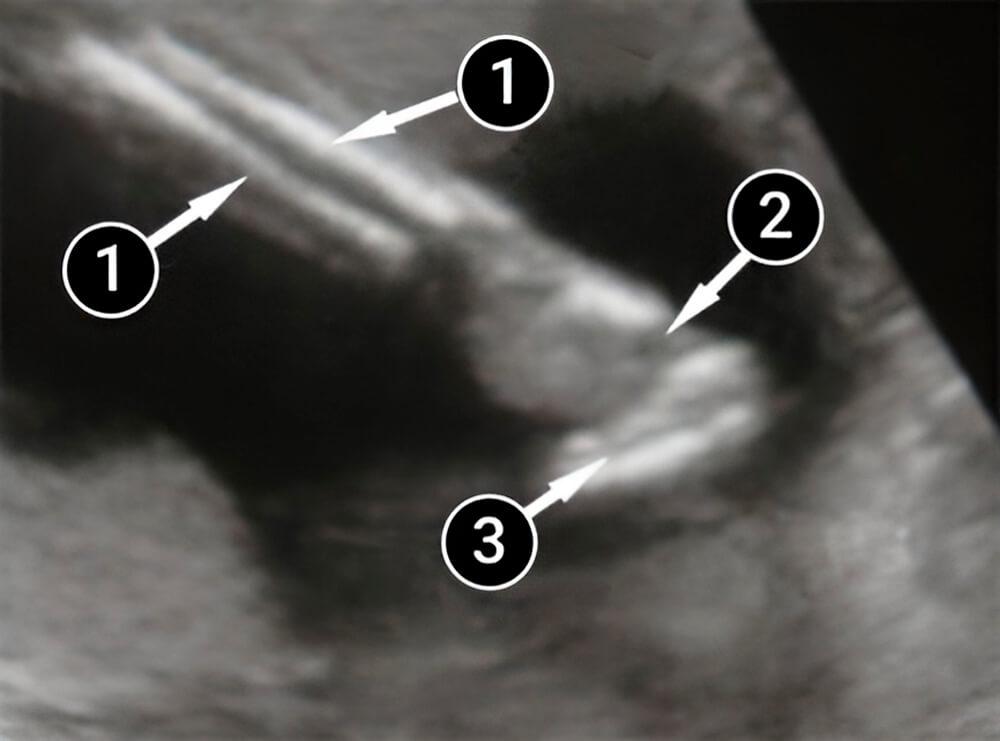

Qué podemos ver en un ultrasonido

La imagen muestra la mano del bebé. En la esquina superior izquierda se ve el radio o hueso del antebrazo. Debajo podemos ver una palma abierta, el pulgar y los otros cuatro dedos.